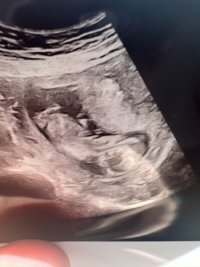

Ultrason görüntüsüne göre bebeğimin cinsiyet tahminini yapar mısınız ?

Ultrason görüntüsüne göre bebeğimin cinsiyeti ne arkadaşlarım. Ben aranıza yeni katıldım yardımcı olabilir misiniz meleklelr ?

Hayatım elinde başka resim var mı NUB a göre cinsiyet tahmini yapmak isterim ama bu resim malesef yetersiz baya parlamış görünmüyor apış bölümü :D:D

Şu isaretledigim yere dikkatli bakabilir misiniz orası cinsiyet ama biseye benzetemedim

Selamlar bi tanem vallahi tam olarak hatta hiç bişi göremiyorum daha daha doğrusu, ilgili resimdeki veri, cinsiyet tahmini için yeterli değil. Bak hemen aşağıdaki nub teorisine göre bebek cinsiyet tahmini yapmak istiyorum ama o alan yok aşağıdaki konuyu incele bitanem.